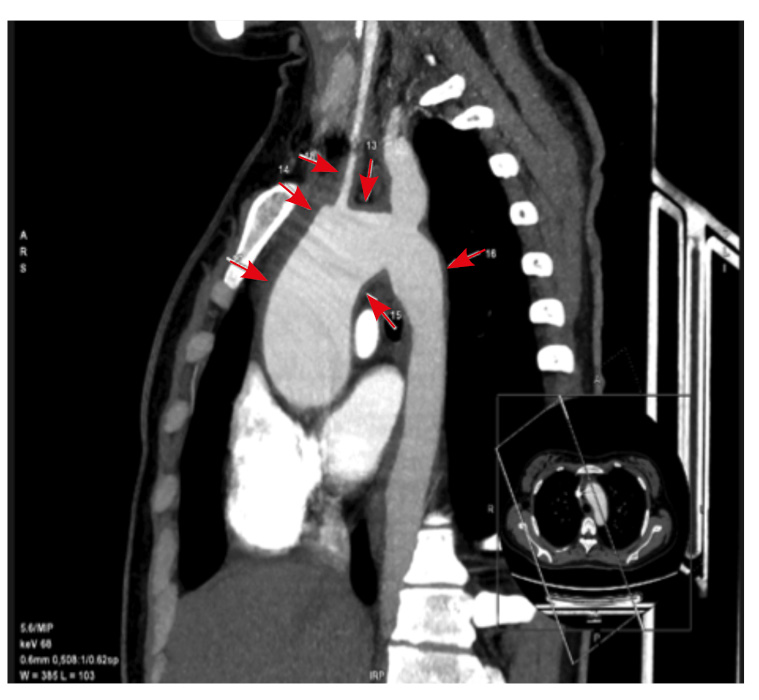

Учитывая сохраняющуюся выраженную слабость, головокружение, субфебрильную температуру, высокий уровень провоспалительных маркеров (табл. 5), отрицательные результаты микробиологического посева крови, повышенный уровень IgA 6,74 г/л (норма 0,82–4,53 г/л), уровень IgМ 2,09 г/л (норма 0,46–3,04 г/л), IgG, 20,40 г/л (норма 6,50–16,00 г/л), принято решение о повторном проведении КТ грудной клетки с внутривенным контрастированием (рис. 3), по данным которого отмечалось расширение просвета корня аорты до 42 мм (норма у женщин – до 35 мм). При контрастировании рисунок легочных артерий симметричный, не обеднен, без дефектов. Легочный ствол диаметром до 21 мм, правая главная легочная артерия – 9 мм, левая – 17 мм. Определяется протяженное утолщение стенок дуги аорты, плечеголовного ствола, общих сонных и подключичной артерии слева. На этом фоне просвет левой общей сонной артерии сужен до 50%. Отмечается веретеновидное расширение просвета подключичной артерии слева до 18 мм на протяжении до 30 мм. Заключение: КТ-данных за патологические изменения легких, а также за патологию контрастирования легочных артерий не получено. КТ-0. КТ-картина аорто-артериита (болезнь Такаясу?) со стенозированием левой общей сонной артерии до 50%. КТ-признаки аневризмы подключичной артерии слева.

Рис. 3. Компьютерная томография грудной клетки с внутривенным контрастированием (07.04.2022). Стрелками указан участок стенозирования левой общей сонной артерии до 50% и аневризмы подключичной артерии слева